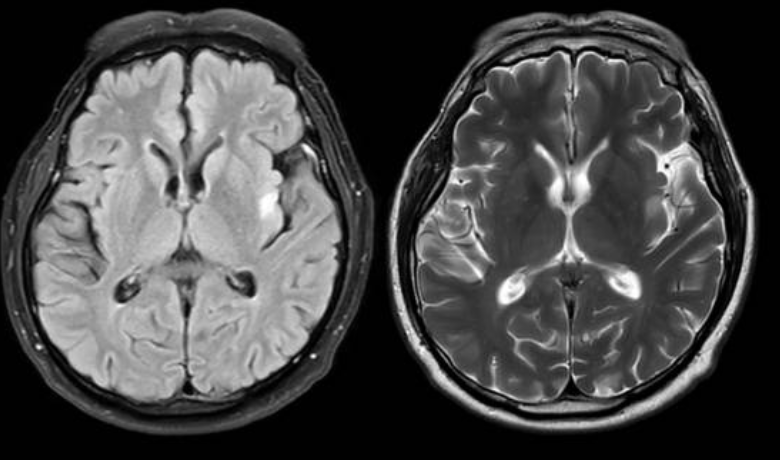

치매의 진단은 단순히 기억력 테스트만으로 이뤄지지 않는다. 전문의는 신경심리검사, 뇌 영상검사(MRI·PET), 혈액검사, 유전자 검사 등을 종합적으로 시행해 원인과 병기를 평가한다.

특히 MRI는 뇌 위축의 정도와 뇌혈관 손상 여부를 확인하는 데 필수적이다. PET-CT는 대사 저하 부위를 시각화하여 치매 유형을 감별할 수 있다. 혈액검사에서는 갑상선 기능 이상, 비타민 결핍, 감염 등 가역적 원인을 감별한다.